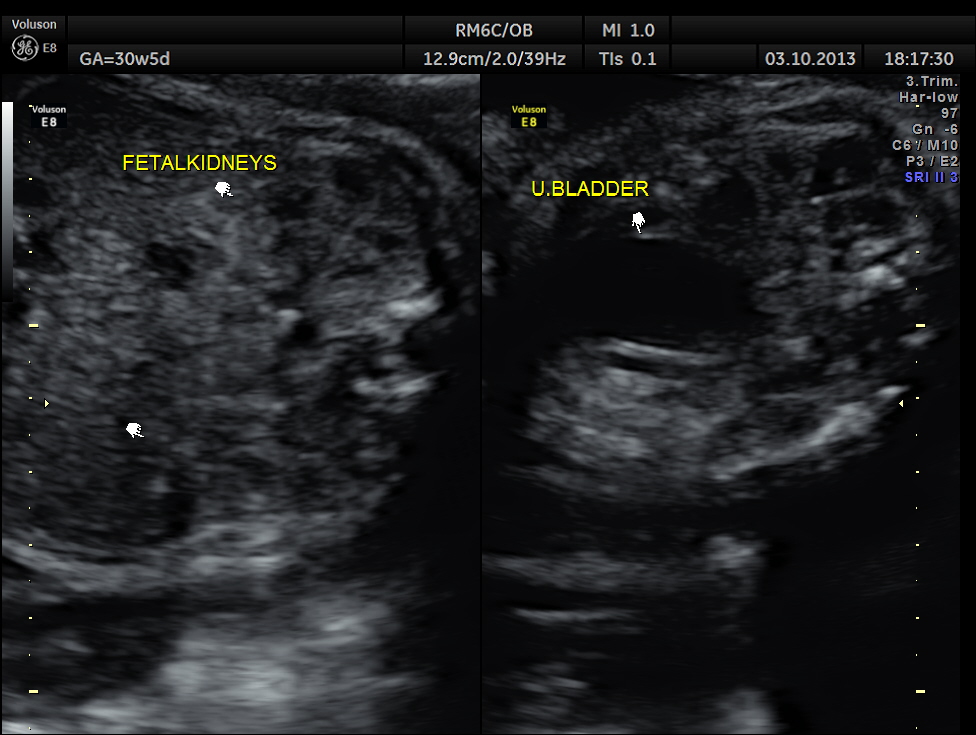

The rest of the scan appeared normal.